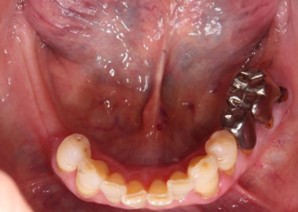

70代 女性

治療前

治療後

治療後- リスク・副作用

- 術後疼痛、歯肉腫脹

- 治療の費用

- 合計¥587,000(税込)

【内訳】

インプラント(1本)¥440,000

その他費用¥147,000

(薬・注射・レントゲン・CT・データ分析・サージカルステント・血液検査) - 年齢/性別

- 70代/女性

- 患者の具体的な症状

- 下顎の奥歯が義歯で噛みづらいため、インプラント治療を希望

- 検査方法

- コーンビームCT、レントゲン撮影

- 診断結果

- 左下6欠損

- 治療詳細

- 左下6インプラント埋入1本、骨造成なし、局所麻酔

- 通院回数

- 8回

- 治療期間

- 6か月